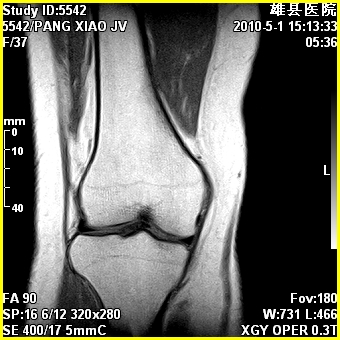

标题: MRI2894:患者右膝关节疼痛两月余,无明显外伤史 [打印本页]

标题: MRI2894:患者右膝关节疼痛两月余,无明显外伤史

右股骨下端前内侧类圆形异常信号,位于干骺端,呈长t1长t2改变,但信号不均,t1图上病灶中心见小片状稍高信号影,t2图上见散在稍低信号影,stir像呈高信号,因病灶较小,缺乏特征性改变,结合患者年龄及部位,考虑嗜酸性肉芽肿可能性大。胫骨关节面下的小囊状异常信号,如果一元论考虑则为嗜酸性肉芽肿,不过发生在这个部位的少见,二元论考虑为邻关节骨囊肿。半月板与前后交叉韧带均未见异常。

右股骨下端前内侧干骺端囊性良性病变,考虑 1内生软骨瘤 2骨囊肿 3肉芽肿。